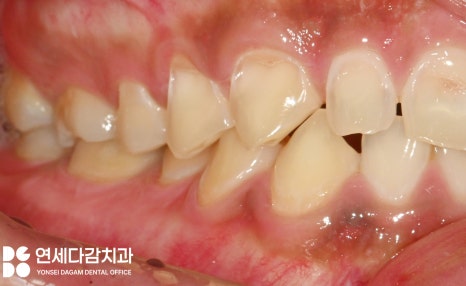

해당 사진을 보면 치아가

닳아 있는 형태를 띠고 있습니다.

그뿐만 아니라 심하면 마모를 넘어서

이렇게 치경부에

굴곡 파절이 생기기도 합니다.

해당 케이스는

평소 탄산음료를 즐겨 먹고,

역류성 식도염과

수면 중 이갈이 습관을 가졌을 때

나타난 구강 모습입니다.

이렇게 파절된 수준이 되면

상아질 구조가 드러나

이 시림 증세가 더욱 심해지게 됩니다.

그뿐만 아니라

어금니 부위에 교모증이 심해지면

교합이 깊게 맞물리면서

수직 고경이 낮아질 수 있습니다.

문정동 치과 에서 보여드리는

케이스도 낮아진 모습을 보이고 있는데요.